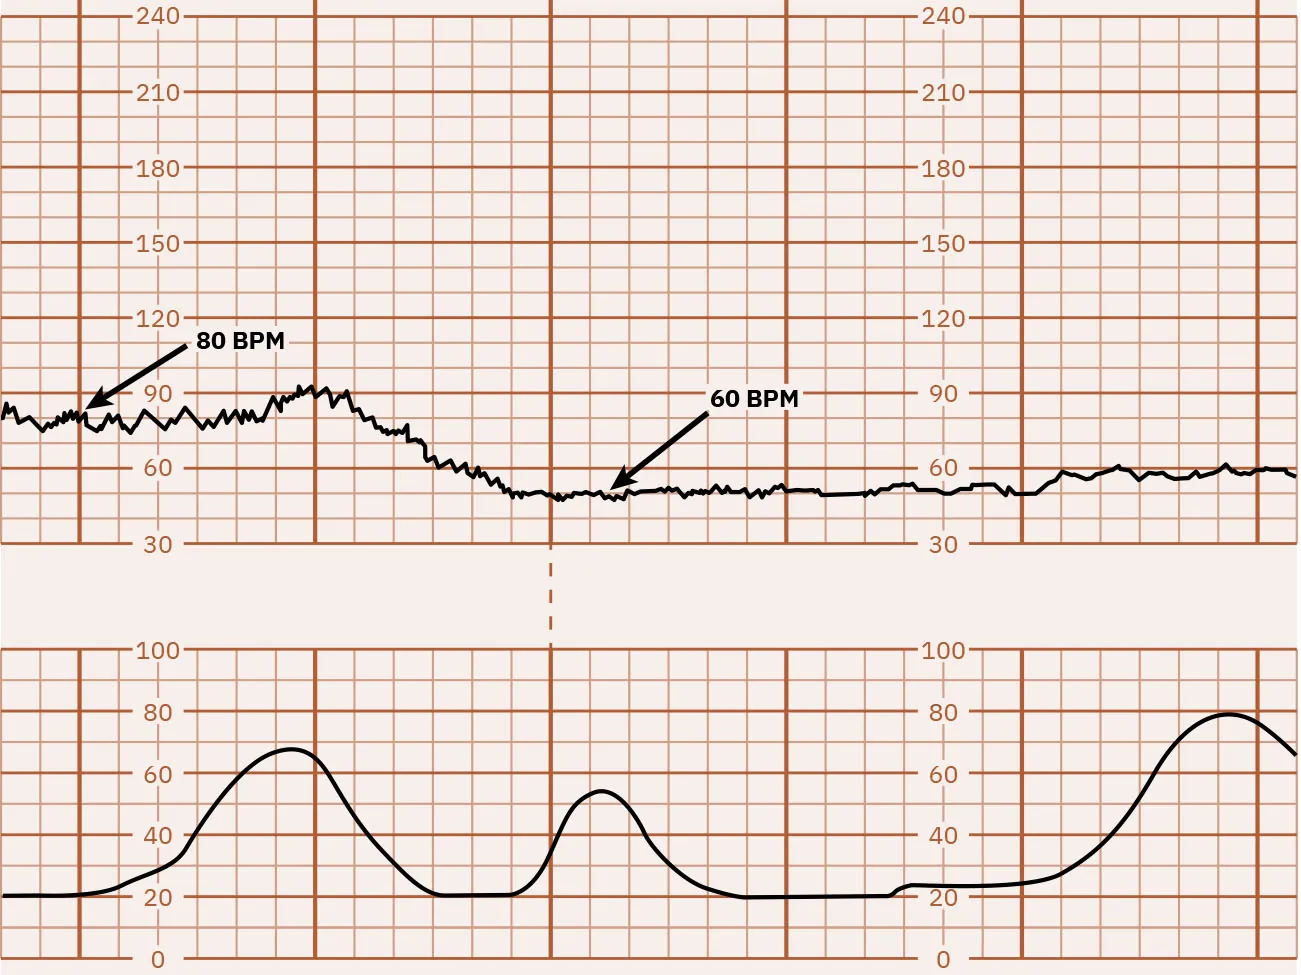

Fetal bradycardia is defined as an FHR baseline less than 110 beats for 10 minutes. Figure 16.4 shows a monitor tracing that indicates FHR bradycardia. Bradycardia can be caused by multiple factors. The nurse must determine if the decrease in FHR is a benign episode of bradycardia or a pathologic prolonged deceleration (possibly lasting several minutes) that may need further intervention. Initial nursing actions for fetal bradycardia include repositioning the laboring person, administering intravenous (IV) fluid bolus, then notifying the health-care provider. See Table 16.2 for risk factors for fetal bradycardia.

Fetal heart rate reading indicating bradycardia.

Figure 16.4 Bradycardia This monitor tracing indicates bradycardia because the FHR is less than 110 bpm. (attribution: Copyright Rice University, OpenStax, under CC BY 4.0 license)